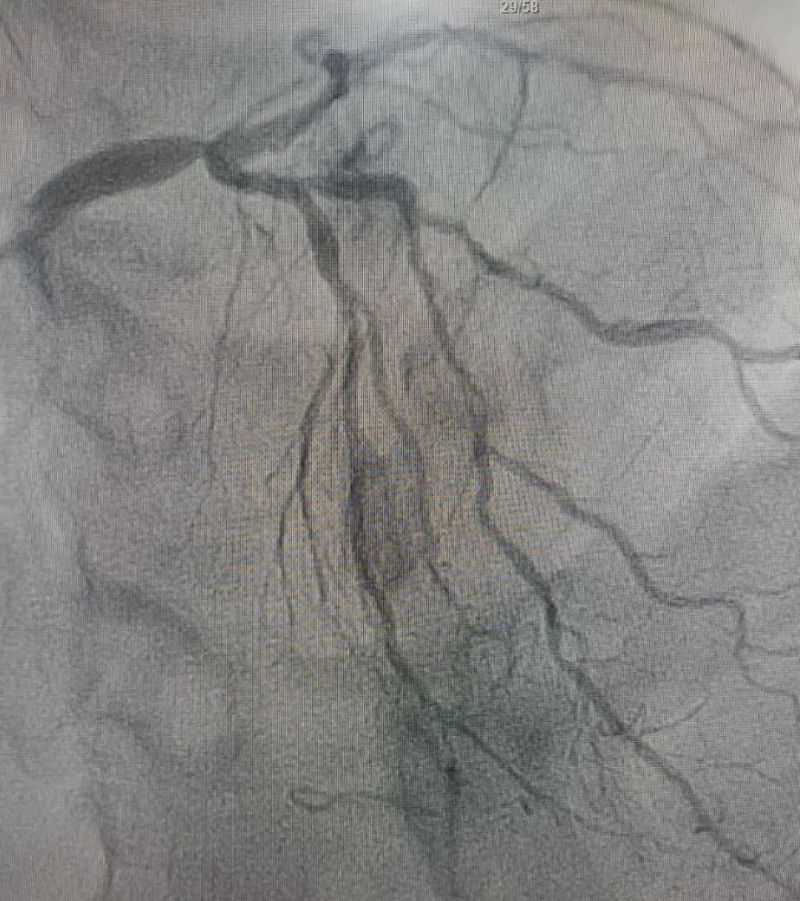

術(shù)中造影顯示,左主干至前降支近段重度狹窄——這正是導(dǎo)致心臟缺血、誘發(fā)室顫的“罪魁禍?zhǔn)住?。主動脈球囊反搏植入、球囊擴張、支架植入......介入團隊精準(zhǔn)操作,一氣呵成。堵塞的血管順利開通,血流重新涌動,這顆一度瀕臨停跳的心臟終于重獲生機。

冠狀動脈造影圖

術(shù)后(左主干至前降支近段原狹窄消失)